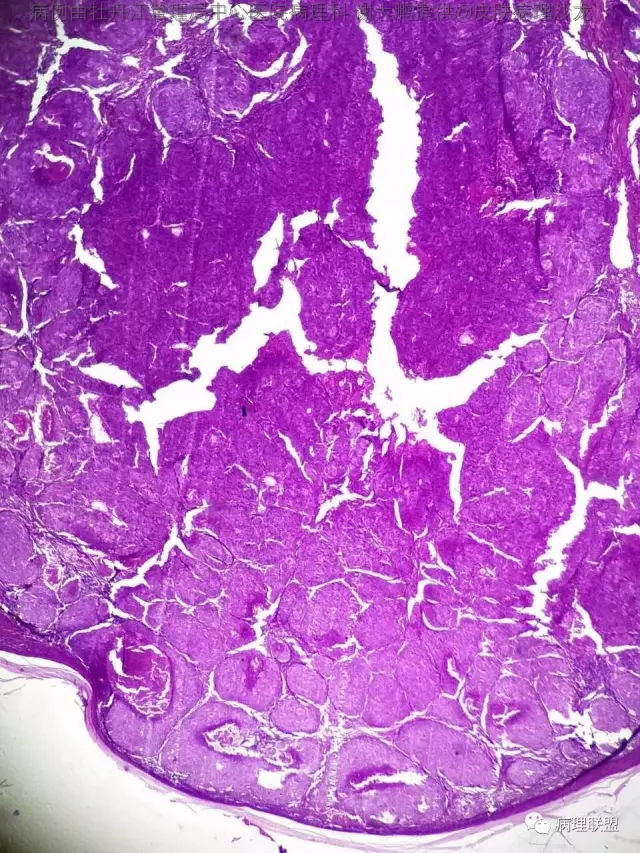

69岁,鼻翼肿物2年,1.5厘米大小,麻烦老师们帮忙看看,谢谢(病例由牡丹江管理局中心医院病理科 谢大鹏提供,致谢!)